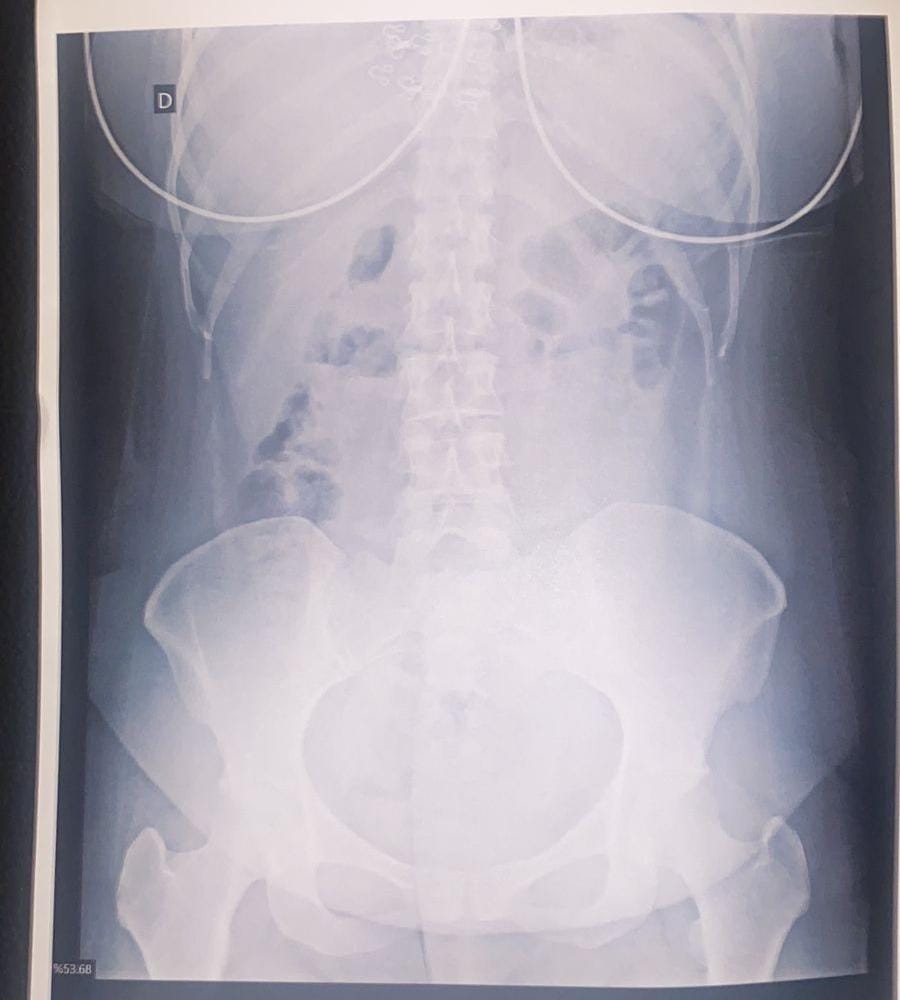

O suspeito, também, declarou que havia ingerido algumas das cápsulas e foi levado à Santa Casa de Corumbá. Ele foi submetido a um exame de Raio-X, que constatou aproximadamente 30 cápsulas ingeridas. No total, foram identificadas 95 cápsulas de droga sob porte do casal.